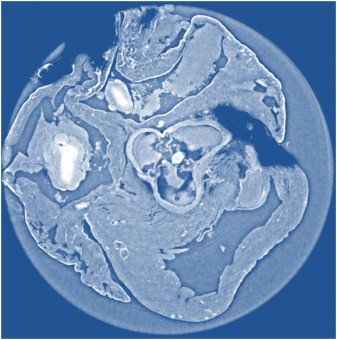

Immagine ottenuta in modo non invasivo della sezione del tessuto cardiaco di un topo realizzata con tomografia X a contrasto di fase “propagation-based”, metodo che fornisce immagini più nitide, e con una risoluzione superiore, rispetto agli altri due considerati nello studio. Crediti: Irene Zanette/Technische Universität München

È infatti con raggi X di alta qualità prodotti dalla radiazione di sincrotrone che un team di scienziati, sfruttando l’acceleratore della European Synchrotron Radiation Facility (ESRF), ha messo a confronto tre diverse tecniche di tomografia a contrasto di fase: interferometrica con reticolo, propagation-based con ricostruzione di fase single-distance e olotomografia. I risultati sono pubblicati sull’ultimo numero del Journal of Applied Physics, e dicono che i tre metodi, per quanto riguarda il loro impiego in ambito diagnostico, sono complementari.